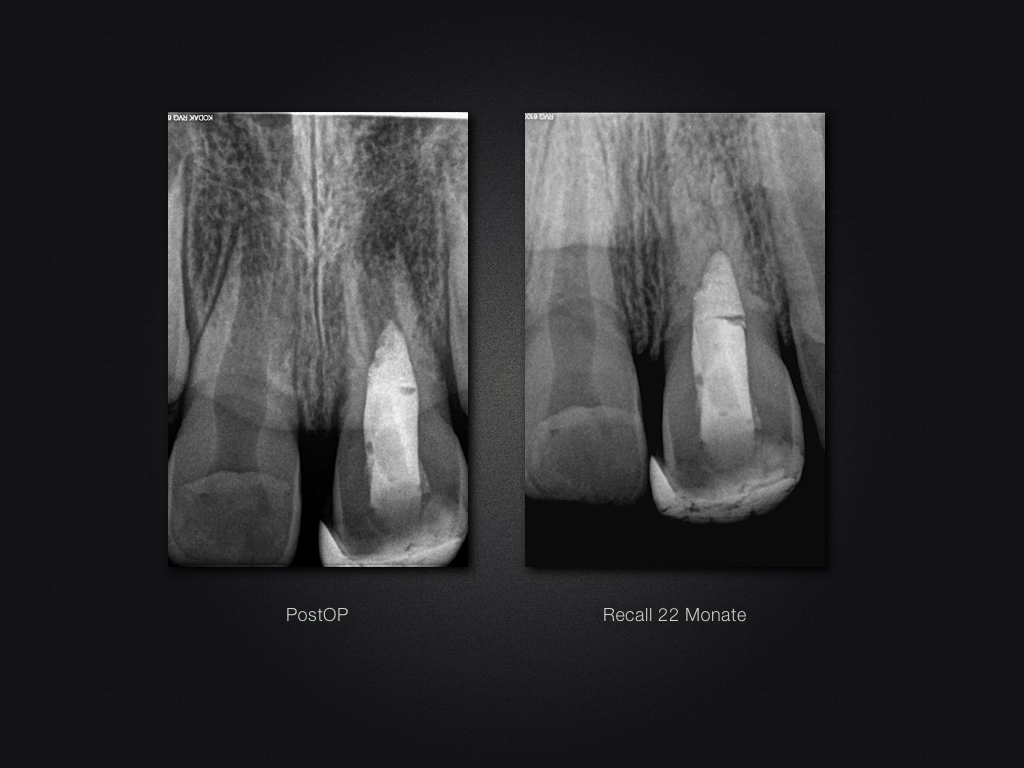

Praxistauglicher Kompromiss